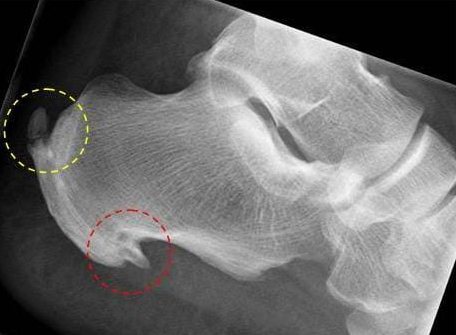

Röntgenbild Fersensporn

Das Röntgenbild zeigt eine Ferse mit typischer Fersenspornbildung:

- dorsaler Fersensporn (gelber Kreis)

- plantarer Fersensporn (roter Kreis)

(Bild: Orthopädie)